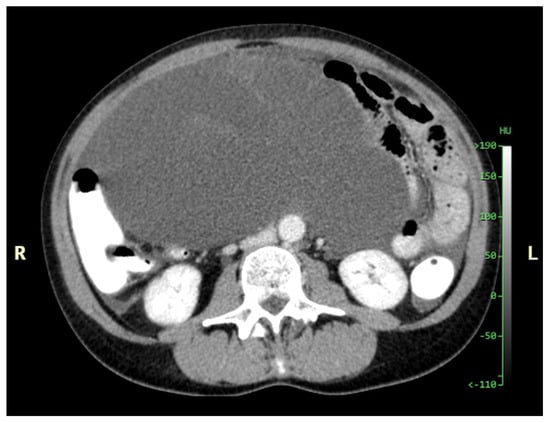

Figure 11. CT, venous phase, axial plane.

Figure 11, Figure 12, Figure 13, Figure 14 and Figure 15. Advanced stage of the disease. The abdomen is full of tumors and mucin. Typical signs are heterogeneous or hypodense masses in the form of lobules often with septa, which could be enhanced by contrast and could be associated with calcifications.

Patients with a misdiagnosed rupture of the mucocele may develop pseudomyxoma peritonei. It is characterized by the presence of an abundant gelatinous substance in the abdomen. Diffuse, progressive, and abundant mucin-containing tumor cells are typical of this disease [2] (Figure 11, Figure 12, Figure 13, Figure 14, Figure 15 and Figure 16). The interval between rupture and advanced disease is several years. In our clinical series, the interval was about 5 years. In the literature, we found a wide range of this interval from 12 months to 10 years [9,10]. The natural history of PMP revolves around the “redistribution phenomenon”, whereby mucinous tumor cells accumulate in the Douglas pouch, in the diaphragm (more on the right), and the small and large omentum (Figure 17). The small intestine is less involved [4]. Pseudomyxoma peritonei is a slowly progressing disease, which fills the peritoneal cavity over time. There are several classifications of pseudomyxoma. The most commonly used is the PSOGI classification [2]. Mucinous accumulation progresses to malnutrition, bowel obstruction, and respiratory compromise. Rarely, the tumor may spread to the pleural cavity. This has been described in 5.4% of cases. It may occur spontaneously or as a result of diaphragmatic injury during cytoreduction [8,11].